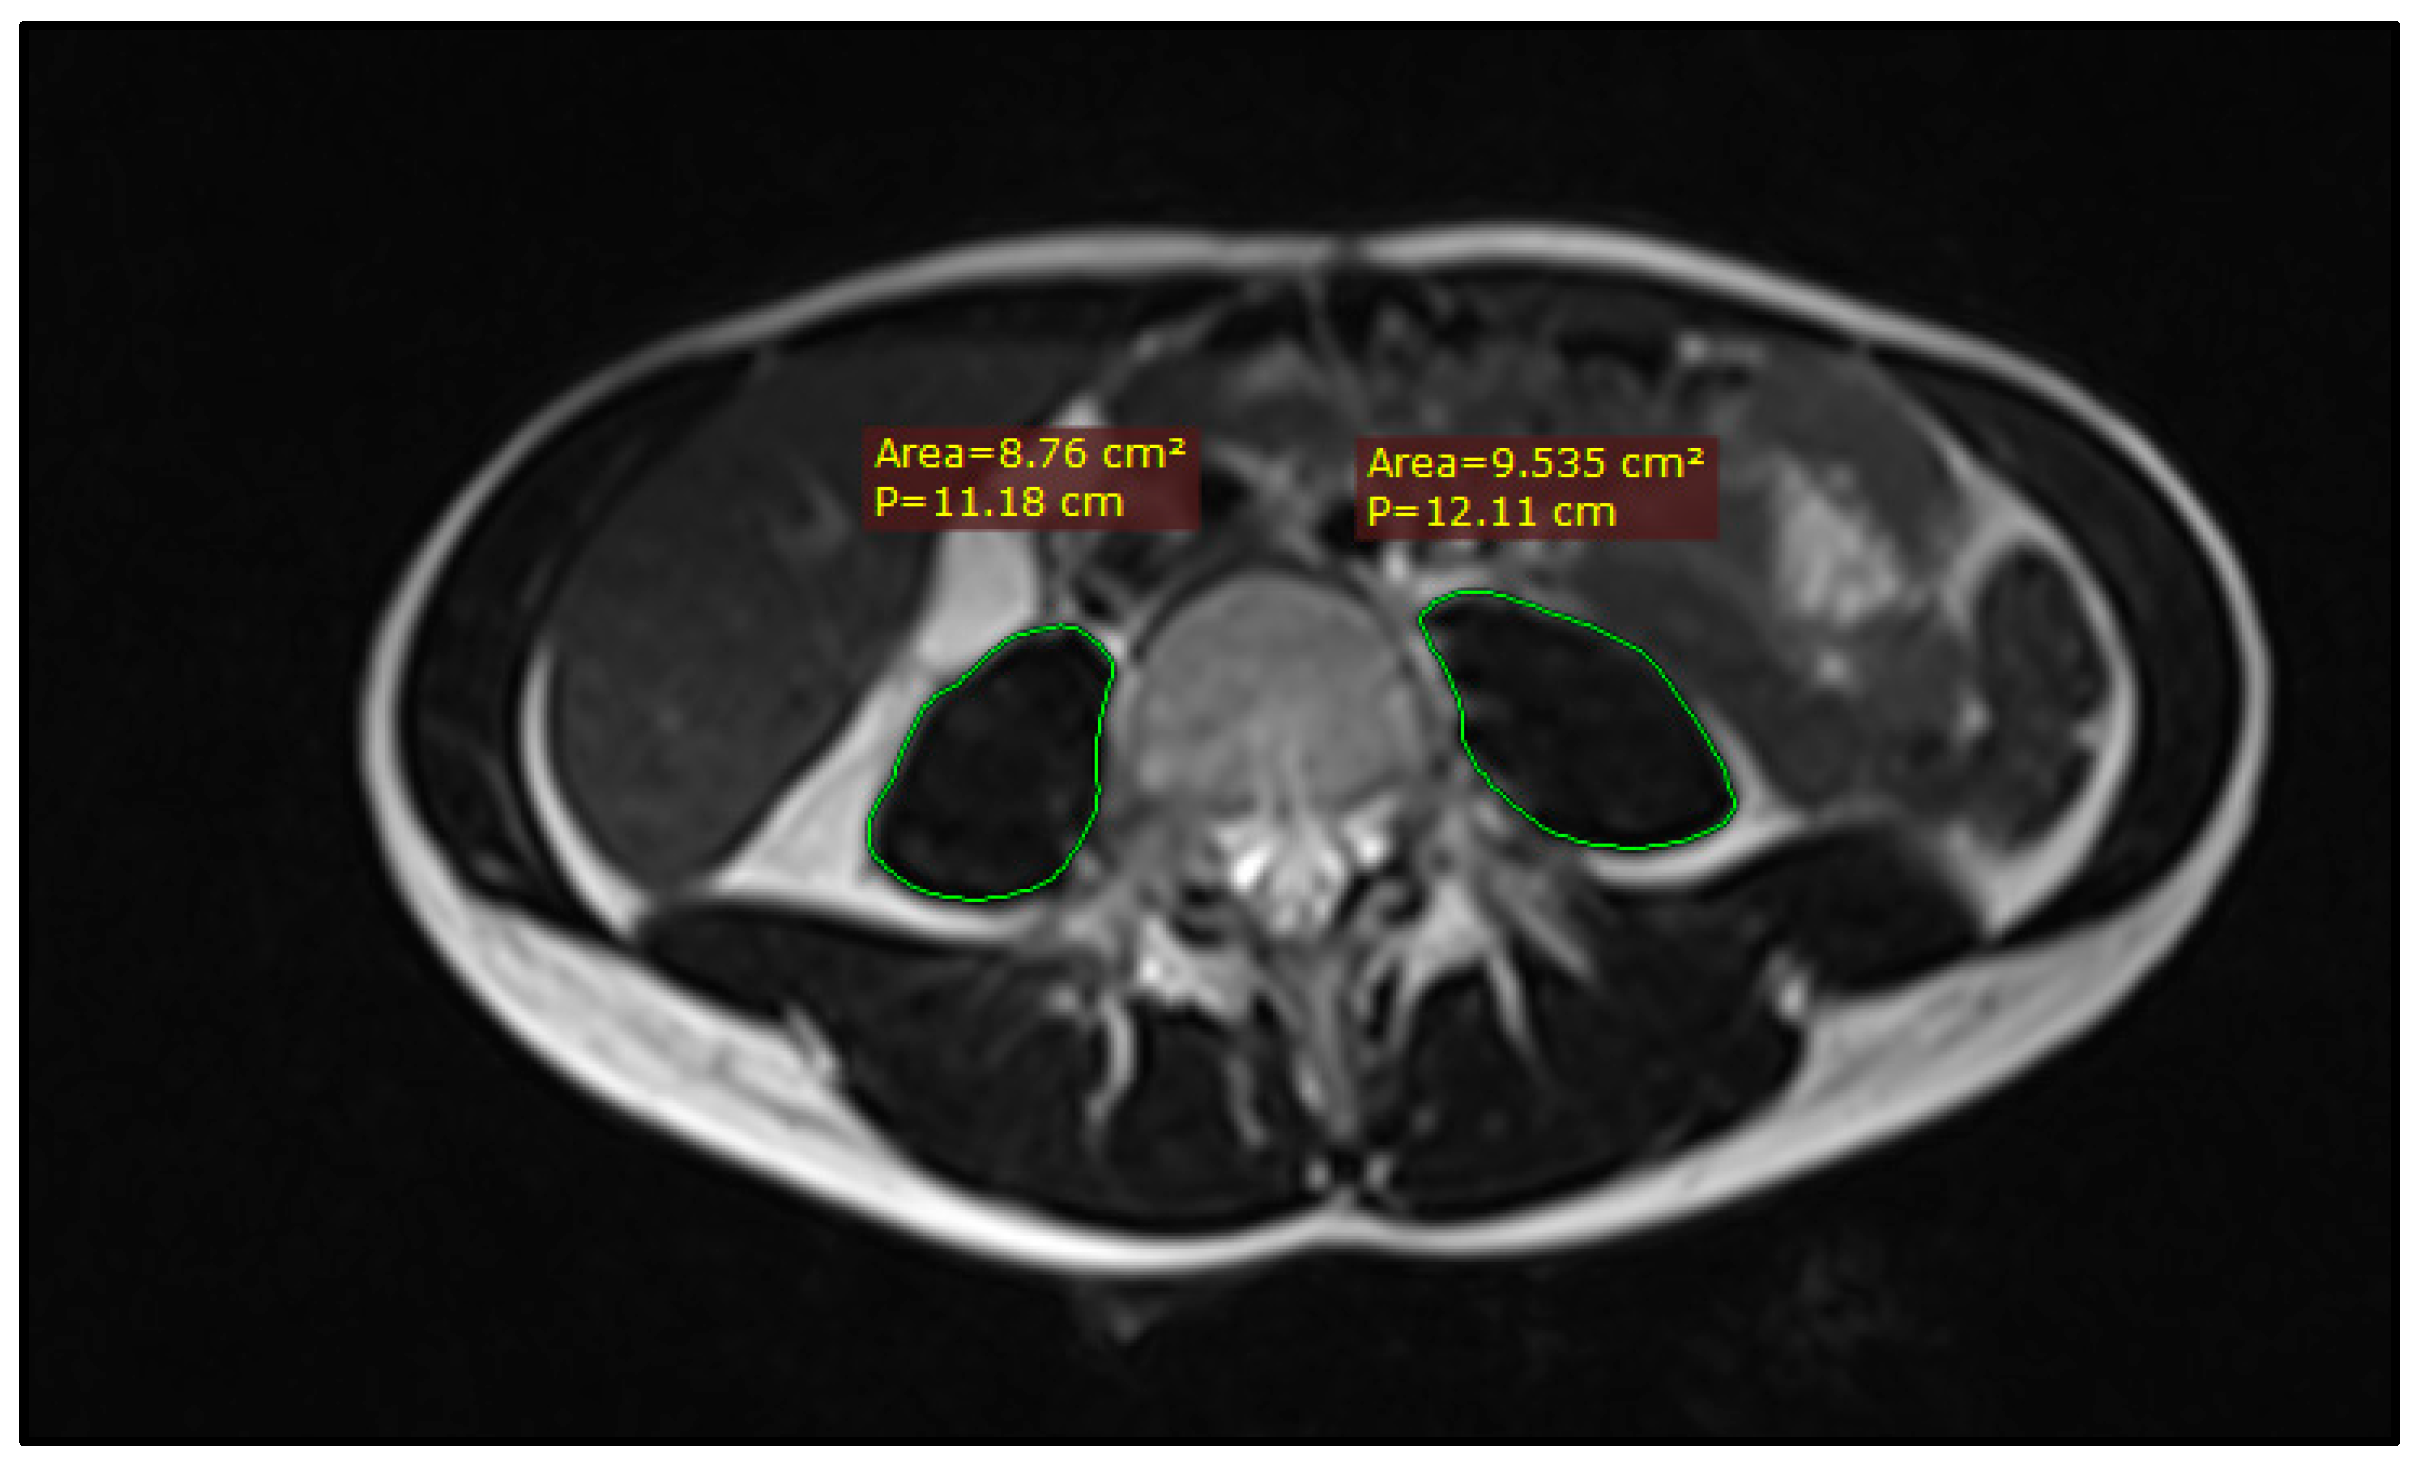

2.2. Sarcopenia Measurement

| Psoas muscle area (cm2) | 23.7 (13–40.8) | 18 (13–22) | 25.5 (15.3–40.8) | 0.001 |